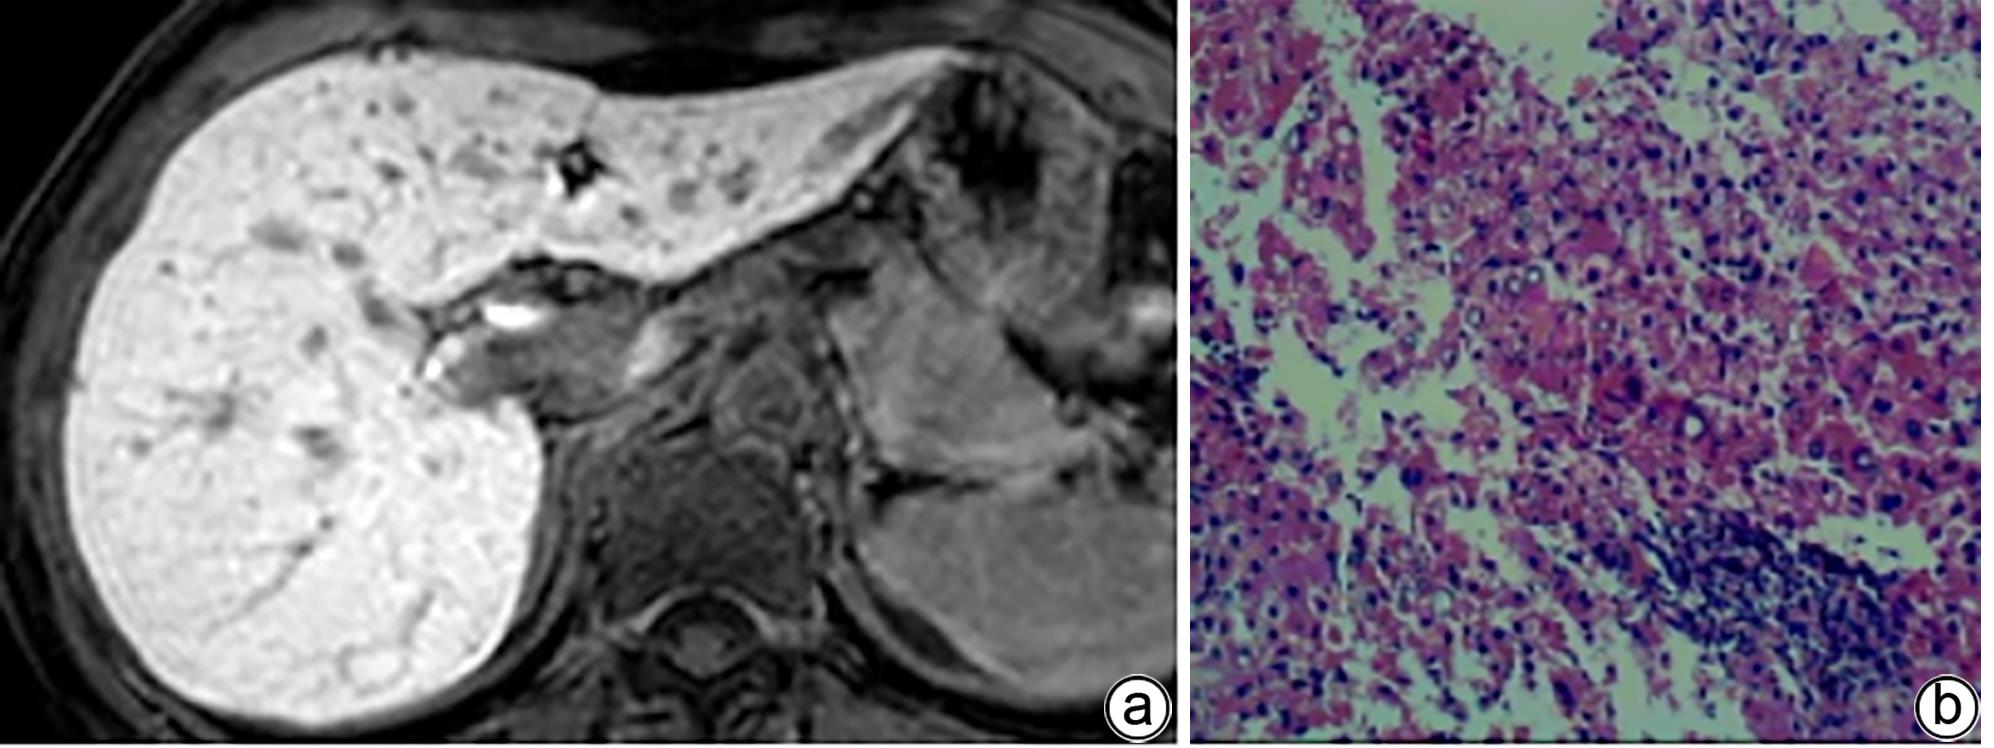

注: a,女,52岁,胆汁排泄期示,胆道各区模糊可见,胆道评分2分;b,肝活检病理(HE染色,×200),镜下见肝小叶结构存在,部分肝细胞排列稍紊乱,小灶见碎片状坏死;汇管区扩大,可见淋巴细胞浸润及纤维组织增生。免疫组化:Hepar-1(+),HBsAg(+),CK7(+),符合慢性乙型肝炎改变(G2S2)。

图 2 肝纤维化S2期MRI增强扫描及肝活检病理结果

Figure 2. MRI enhanced scan image of the bile excretion phase of the S2 stage of liver fibrosis + Pathological image of liver biopsy

注: a,男,36岁,胆汁排泄期示,各区均可见,但部分胆管或汇合处未见显示,胆道评分3分;b,肝活检病理(HE染色,×200),镜下见肝细胞排列紊乱,可见点灶状坏死及碎片状坏死;汇管区扩大,淋巴细胞浸润及纤维组织增生。免疫组化:Hepar-1(+),HBsAg(+),CK7(+),符合慢性乙型肝炎改变(G2S3)。

图 3 肝纤维化S3期MRI增强扫描及肝活检病理结果

Figure 3. MRI enhanced scan image of the bile excretion phase of the S3 stage of liver fibrosis + Pathological image of liver biopsy